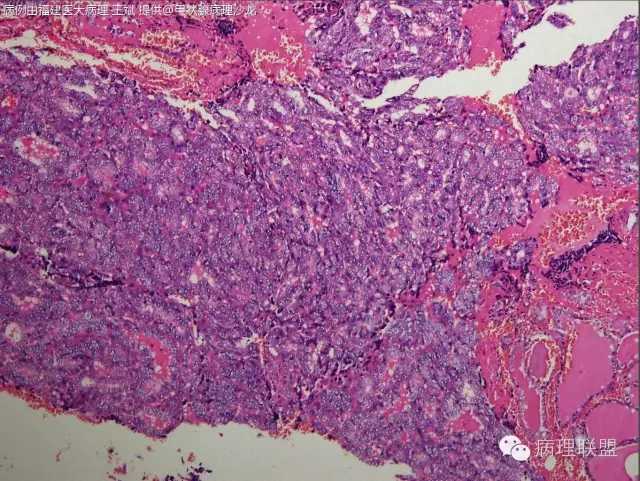

核的特征不明确,是不是得考虑滤泡癌。

滤泡癌和滤泡亚型PTC预后及治疗有何区别?韩帅,我觉得核的特征还是有的@河南新密人医病理科韩峰楼

有少量核沟,如果核够就是滤泡亚型ptc

此片中所显示的“核特征”为人工现象,滤泡癌。

我赞同FTC

@福建医大病理 王斌 这种生长方式就是癌,无论免疫组化如何表达或不表达